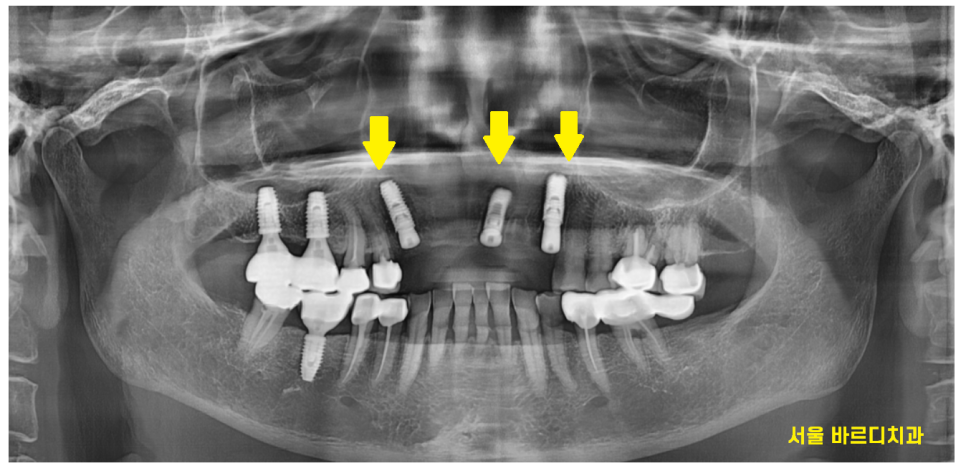

아주 오래전 앞니를 치료 받았는데

문제가 생겼다고 하남미사치과를 방문을 해주셨습니다.

송곳니부터 송곳니까지

앞니 6개를 묶어놓은 형태로 치료를 하셨더라고요~

치아는 문제가 많았습니다.

충치가 많이 먹은 송곳니

기둥까지 넣어 보강한 치아의 실금

양쪽 송곳니 두개 다 문제가 있었습니다.

결국 문제가 되는 치아들을 발치 후

앞니 브릿지 교체를 진행하기로 상담해드렸습니다.